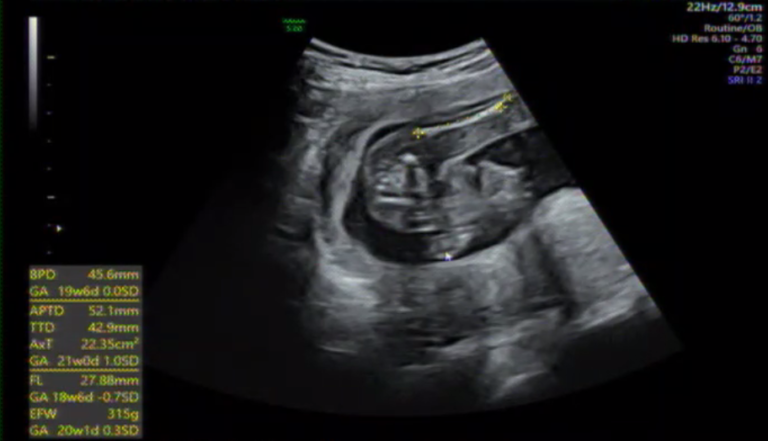

Efw エコー 平均-慢性心不全:診断と治療の進歩 トピックス 355 日本内科学会雑誌 第101巻 第2号・平成24年2月10日 図1 心エコー・ドプラ法を用いた左室充満圧の推定(米国心エコー図学会1)) e/a:僧帽弁口血流速波形の拡張早期(e)波高と心房収縮期(a)波高の比,dt:e波のピークからの減速時間, EFW 636g(23w5d) 26w3d BPD 640mm(25w5d相当) FL 445mm (25w5d相当) AC 63mm(26w0d相当) EFW 849g(25w5d相当) 1エコー誤差もあるとは思いますが、赤ちゃんの成長が少しゆっくりめになってきてしまってるのでしょうか?

妊娠週 32w4d 32w4d、 BPD(児頭大横径)=868mm、 AC(腹部周囲長)=2619mm、 FL(大腿骨長)=597mm、 EFW(推定胎児体重)=1928g、 性別=男、 4Dエコー おなまえ ゆみ ねんれい 40 妊娠週 32w4d やっと顔を見せてくれました♪08グラムの女の子です (*^^*)一人目妊婦の約半数が「小さめ」といわれ、約 エコーの時うちの子はbpd(頭の幅)が平均値よりも大きかったので、難産になるのかな?まさか障害が?と不安がいっぱいでしたが実際は大丈夫でした。平均値のデータも載せています 妊娠4ヶ月 受精から84~90日目胎児の推定体重は、先ほどエコーで測定した胎児の頭位・腹囲・大腿骨長を元に、次の式で計算します。 efw(g) = 107 × bpd3 030 × ac2 × fl レッサー母さん 赤ちゃんは生まれてから1年間で、めざましい成長をします。

EFW・=1.07 BPD (の3乗) 十 3.00 × 10 (の-1乗) AC (の2乗) × FL ◆EFW (g) 体重の平均値(週数別※数値は0日目) 18W:187 19W:247妊娠週 30w4d 30w4d BPD(児頭大横径)=802mm AC(腹部周囲長)=2441mm FL(大腿骨長)=559mm EFW(推定胎児体重)=1551g 性別=男 4Dエコー おなまえ ぺちたん ねんれい 21 妊娠週 30w4d 凄く綺麗に3Dエコーが撮れました。 私の病院はたまにしか3D無かったのでCreated Date PM